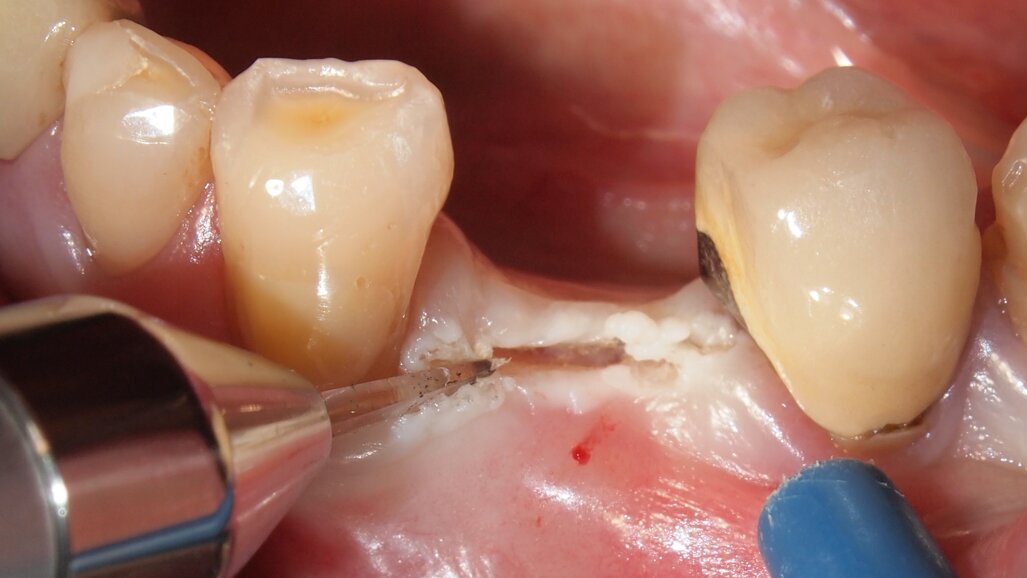

Fig. 3 - Caso clinico 1. Incisione dei tessuti molli con laser a diodi da 915 nm ed inserto in zaffiro. Si osservi l’annerimento della porzione terminale dell’inserto, ad indicarne l’avvenuta attivazione.

Fig. 4 - Caso clinico 1. Incisione dei tessuti molli con laser a diodi da 915 nm e inserto in zaffiro. L’inserto viene condotto lentamente con un movimento simile a quello della lama fredda.

Fig. 5 - Caso clinico 1. Incisione dei tessuti molli con laser a diodi da 915 nm e inserto in zaffiro. Si apprezza macroscopicamente l’assenza di fenomeni di carbonizzazione.